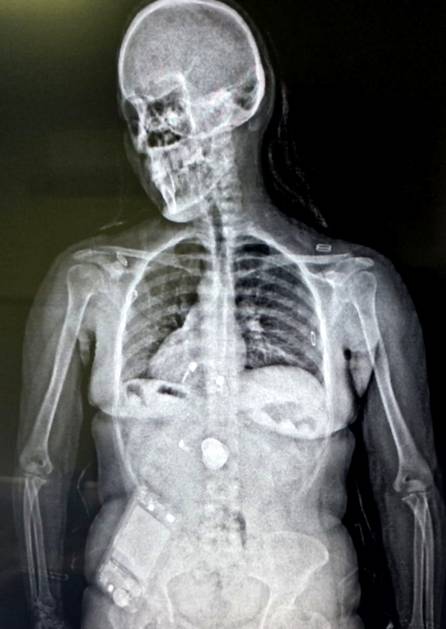

Allí, con la nueva tecnología inaugurada recientemente, se les realizó un escáner corporal que permitió detectar cuerpos extraños en la zona abdominal. Sin embargo, el hombre y la mujer implicados negaron haber ingerido cápsulas con estupefacientes.

Mediante estudios de rayos X, se confirmó la presencia de elementos extraños en sus organismos, por lo que quedaron internados bajo custodia policial.

Horas después, los sospechosos evacuaron un total de 192 cápsulas, 96 cada uno. Mientras que la prueba de campo narcotest arrojó positivo para cocaína y el peso total de la sustancia incautada fue de 2 kilos 200 gramos, cada uno llevaba poco más de un kilo de la droga en su estómago.